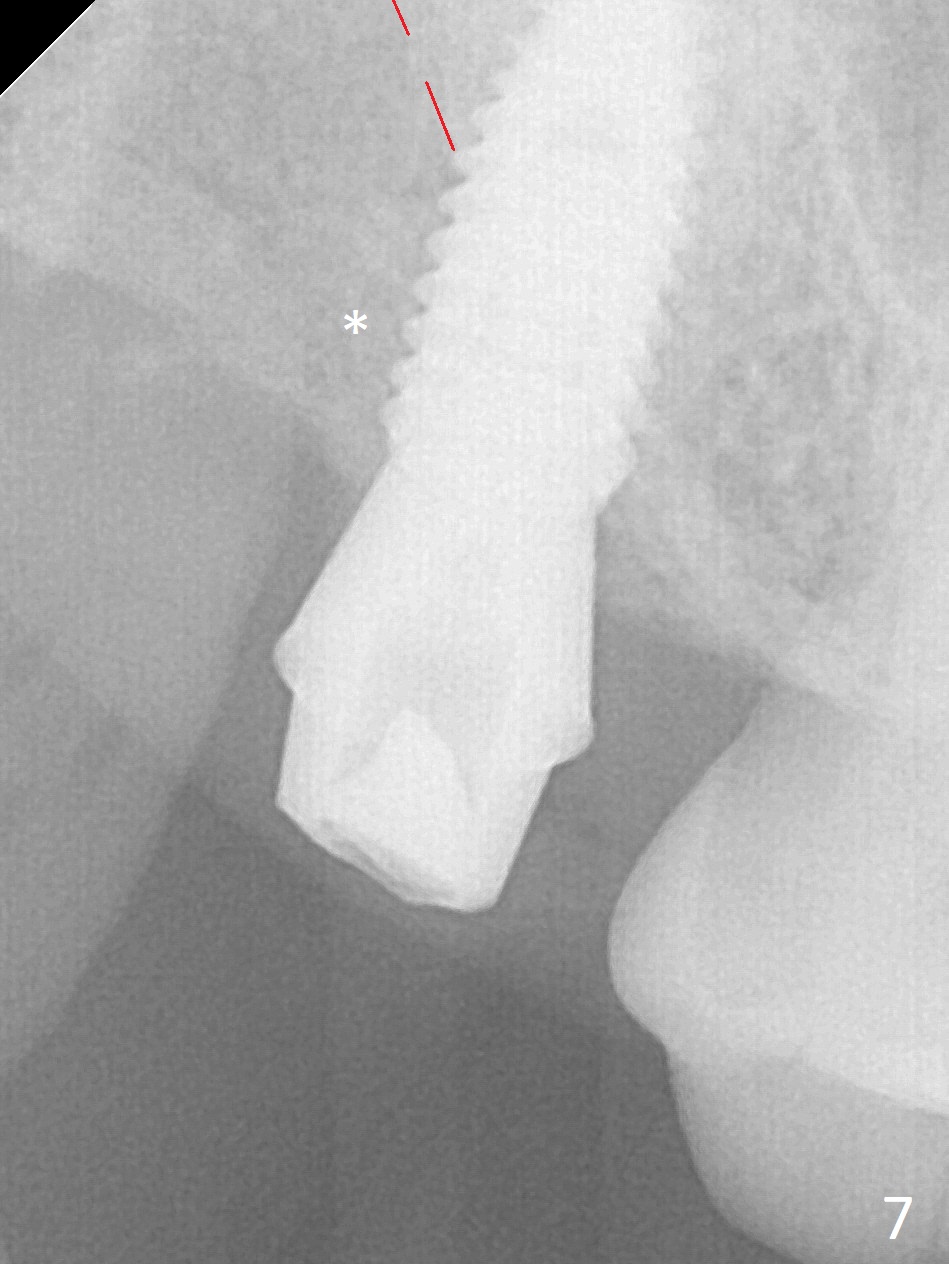

After extraction of the 3rd molar with mesial periodontal defect, osteotomy for 2nd molar implant is initiated in the mesial slope of the 3rd molar socket (Fig.1 red dashed line). When osteotomy is finished with IS drills and sinus lift with Magic Sinus Lifter (S-reamer with 11 mm stopper being short), a 4x10 mm dummy implant is placed with ~ 4 implant thread exposure (Fig.3). Following use of Lindamann bur to move osteotomy mesial and larger drill, a 4.5x10 mm implant is placed with 5-7 implant threads exposed distally (Fig.4,7 (~ 50 Ncm)). The bucco(B)-palatal(P) extent of the implant thread exposure is larger (Fig.5) than that associated with the 4 mm dummy implant (data not shown). The exposed implant surface is covered with Vera Graft (Fig.7*), Collagen plug and an immediate provisional after adjustment of abutment height (Fig.6,7). The bone density distal to the implant is low 3 months postop (Fig.8,9 CBCT) and 3.5 months postop (Fig.10,11). The permanent crown is cemented nearly 4 months postop. The distal cortical bone contacts the implant (Fig.12 ^), while the mesial bone increases in density (*) 2 years postop.